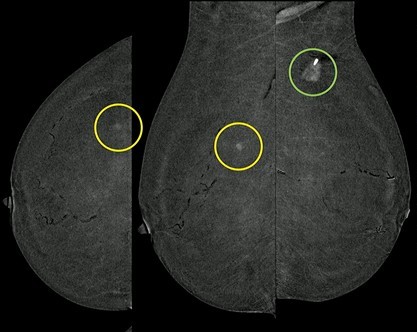

Clinical Pearl: CEM-guided interventions are a game-changer for patients who cannot tolerate MRI. For example, in an 83-year-old patient with invasive lobular carcinoma (ILC) who was not an MRI candidate, CEM-guided localization successfully targeted a contralateral mass that was mammographically and sonographically occult.

• Targeting: Using a combined scout (CEM+DBT) provides the most flexibility for choosing the optimal guidance modality.